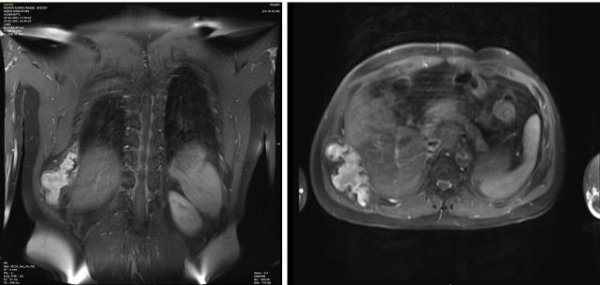

Figure 7,8,9,10, 11, 12

Case 3 - 35 year old male who presented with low back ache since 5 years and swelling since 2 year. Upon evaluation with X-ray of pelvis was found to have a lytic lesion in the left ileum on posterior aspect Fig-7. On MRI T2 hyper-intense lesion was found the posterior ileum with soft tissue component and cortical breech on posterior aspect measuring 5.7x 4.1x 7.3cm Fig-8.. Patient underwent extended curettage of the lesion and reconstruction with Poly-methyl methacrylate cement and Post-op Histopathology showed oval to spindle shaped cells with indistinct cell borders, round to oval hyperchromatic nucleus and moderate amount of cytoplasm- fibromatosis Fig-9. Upon follow up for 3 years patient is disease free.

Case 4- 21 year old female patient who presented with pain and swelling of the left lower back area since 8 months. Upon clinic radiological evaluation – on x ray was found to have a lytic lesion in the left postero-superior iliac wing and MRI showed T2 intermediate to hyper-intense lesion on the left iliac wing with cortical breech and extra-osseous soft tissue component involving the iliacus muscle anteriorly and gluteus medius posteriorly measuring 5.9x5.6x6.3 cm with T2 hypointense rim around the lesion Fig-10. Histopathology proved to be fibromatosis and after multidisciplinary team meeting patient was planned for extended curettage and reconstruction Fig-11. Reconstruction was done using poly-methyl methacrylate cement and two K-wire for stabilisation with post-op Histopathology confirming the diagnosis Fig-12. Upon one year of follow up patient does not have any complaints and doing well.